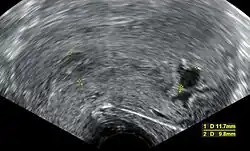

An ultrasound showing a gestational sac containing a yolk sac but no embryo

Mean gestational sac diameter of at least 25 mm and no embryo. Mean gestational sac diameter of 16–24 mm and no embryo. [110][111]

Absence of embryo with heartbeat at least 2 weeks after an ultrasound scan that showed a gestational sac without a yolk sac. Absence of embryo with heartbeat 7–13 days after an ultrasound scan that showed a gestational sac without a yolk sac. [110][111]

Absence of embryo with heartbeat at least 11 days after an ultrasound scan that showed a gestational sac with a yolk sac. Absence of embryo with heartbeat 7–10 days after a scan that showed a gestational sac with a yolk sac. [110][111]